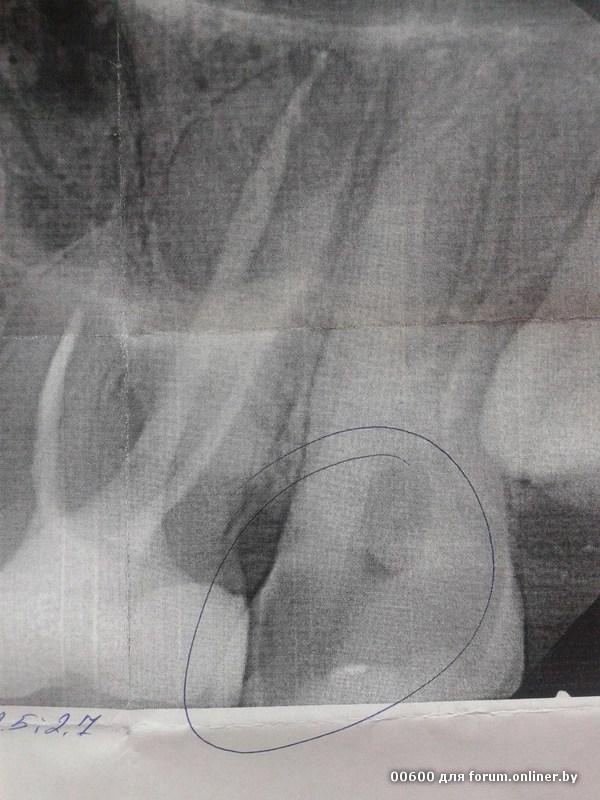

Здравствуйте! Подскажите, пожалуйста, какова учесть этого зуба?

MiKo_:

Может еще пару слов об анамнезе, что конкретно волнует, а то уж очень скудная информация.

Vitas:

Меня еще летом беспокоил этот зуб, не болел, но между 4 и 5 постоянно застревала пища, чувствовала, что что-то не то. Обратилась к врачу, получили другой зуб, а этот решили не трогать, потому как ребенок мой был на ГВ и не захотели делать снимок, всё равно скорее всего протезирование. А недели 2-3 назад начал болеть, отдавало в ухо, потерпела недельку, обратилась в бесплатную стоматологию, сейчас заложили лекарство. И вот вопрос: что сейчас правильно делать с зубом? Чисто внешне, рассверлили треть зуба, более-менее нормально выглядит. Я не профессионал. Как поступить?

Депульпировать, и скорее всего ставить коронку.